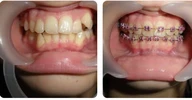

اعوجاج الأسنان